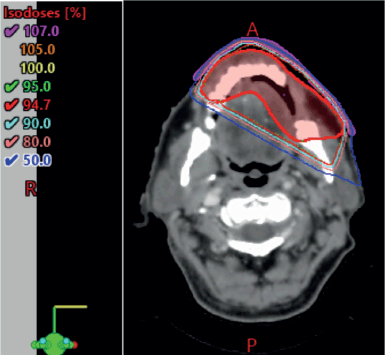

The case was revisited in the tumour board meeting, where the consensus was to proceed with consolidative radiotherapy (RT). Within 6 weeks of completing the sixth cycle of chemotherapy, the patient was scheduled for 3D conformal radiation therapy (3DCRT). Treatment planning done was involved site radiotherapy (ISRT) in which previously Pet avid site of primary lesion was contoured as pre chemo gross tumour volume (GTV) then a clinical target volume (CTV) was generated to include entire site (ISRT) in our radiation field followed by planning target volume (PTV) to incorporate set up error changes. A total dose of 3,600 cGy was delivered in 18 fractions, with 200 cGy per fraction, using 6 MeV energy and a 3 mm bolus to ensure adequate surface dose distribution (Figures 5–7).

Figure 5. 3DCRT plan showing isodose curves.